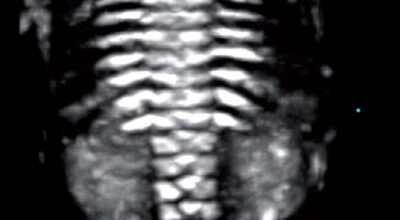

La evolución del feto a través de ecografías

Ecografía de 23 semanas: examen de la columna vertebral y las costillas a través de la ecografía 3D. Este análisis no es sistemático y se realiza cuando hay cierta susceptibilidad de una anomalía de las vértebras o una enfermedad ósea.